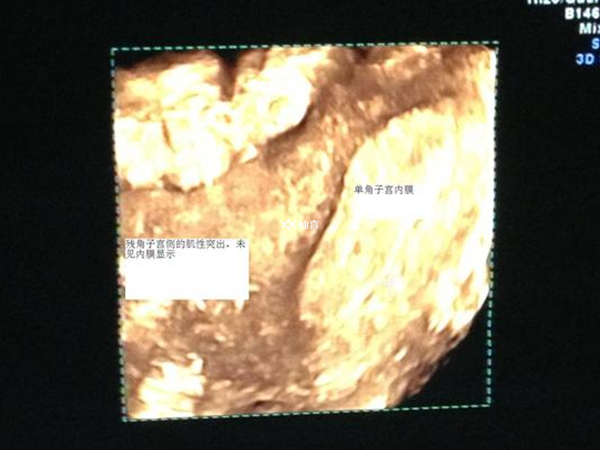

子宫内膜在胚胎着床和发育过程中起着关键作用。如果子宫内膜过薄(一般小于7mm),可能无法为胚胎提供足够的营养和支持,使胚胎难以附着和侵入内膜,因此做好移植前的内膜调理工作非常重要。